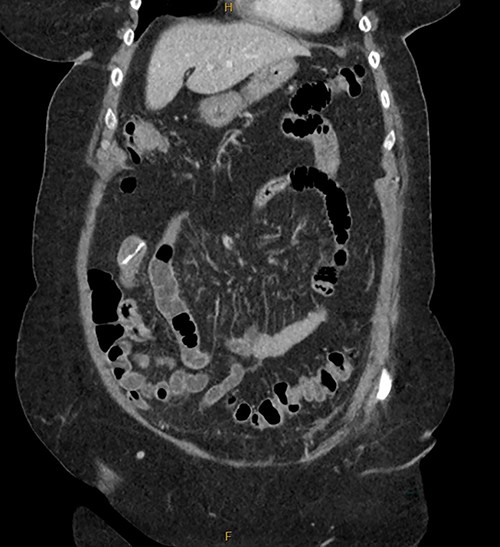

Patient RF a 74-year-old lady with a background of obesity and dyslipidaemia was admitted under the acute surgical care team after experiencing several weeks of diarrhoea, vomiting and a generalized grumbling abdominal pain. Initial abdominal plain films showed a FB in the right middle abdomen (Fig. 3). A follow-up CT was able to highlight this linear hyperdensity which correlated in location to the plain radiographs (Fig. 4). Her laboratory markers were as follows WCC 14 × 109/L, neutrophil count 13 × 109/L, C-reactive protein 57 mg/L. RF herself could not recall a history of FB ingestion. Initially the medical teams had presumed that the FB could have been a fragment of the patients’ denture. RF was placed on a clear fluid diet and daily serial plain films were performed to observe for progression of the FB. On Day 2, interestingly the FB was no longer present on plain films.

Serial CT demonstrated that the FB had progressed, however had embedded itself within a more distal segment of small bowel. A decision was made to resect the affected small bowel and retrieve the FB.

A diagnostic laparoscopy was performed and two segments of concerning small bowel were identified. A mini-laparotomy was performed and the FB was palpable at the distal ileum. An enterotomy was performed and the object was identified as a BC (Fig. 5). Due to the inflamed segment and possible impending perforated serosa, the segment of compromised small bowel was resected, and a hand-sewn anastomosis was performed. The small bowel was walked proximally and a further site of compromised bowel suggestive of an impending perforation was identified and the affected site was resected and repaired.

A significantly degraded clip suggested that the object had been present for a prolonged period. An expiration date could not be seen.

Secondly, as shown in the three cases, unless the BC is calcified, abdominal plain films are not a reliable method of tracking nor diagnosing BC ingestion [9–13]. CT is more sensitive, with a sensitivity rate of 67%, but is not consistently reliable on its own [6, 7]. Reconstructed 3D imaging is effective in identifying BCs. Most BCs are made of low-density polystyrene, a type of versatile solid plastic, which are not readily identified on plain film imaging [14, 15]. This non-degradable plastic means that it is usually only a matter of time before a patient develops a complication.